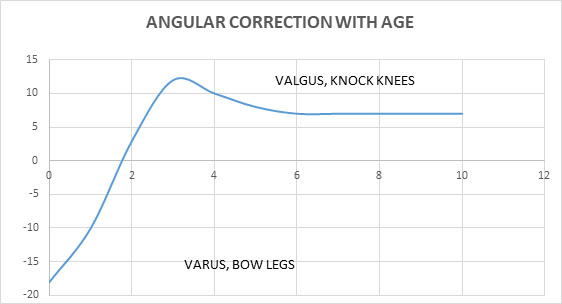

ANGULAR DEFORMITIES OF THE LOWER EXTREMITY

Angular deformities are another essential topic of parental concern. There is a varying and changing pattern of angular deformity, which happens in the knee joint that it is a frequent source of anxiety to parents. Typically a newborn would have bow legs which drifts into valgus by the age of two years and reaches maximum valgus by the age of 7 years and then stabilizes to a mild physiological valgus by early teen ages, which is depicted well in the graph below.

The important point of note is to examine the fingerbreadth distance between the two knees in bow legs and the trans-malleolar distance in knock knees. A vast majority of kids have physiological bowing and are referred more for reassurance than intervention to a pediatric Orthopedist. But, the critical point to remember is that there is a small subset of patients who could have an underlying metabolic disorder that needs to be diagnosed and treated appropriately. The differential diagnosis is rickets, traumatic, or infective growth plate insults, dysplasia, Blount’s disease, and neoplasms. It is essential to investigate adequately if there is associated systemic features, asymmetric presentation. There was a tendency in the past to treat these disease with braces, manipulation and various other intervention but ultimately studies have found that it does not make much difference